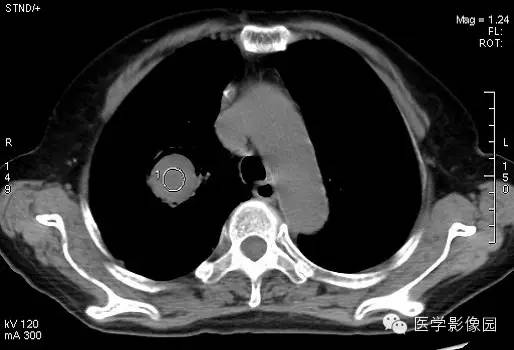

女,80岁,发热咳嗽。

CT表现

右肺内见一圆形空洞病灶,内有圆形曲菌球,边缘光滑,可随体位改变而变动,曲菌球与洞壁之间可见“新月征”。

影像表现为肺内空洞病灶内有圆形软组织密度影,改变体位后曲菌球位置可变动,曲菌球与洞壁见出现一新月形间隙,称为“新月征”。